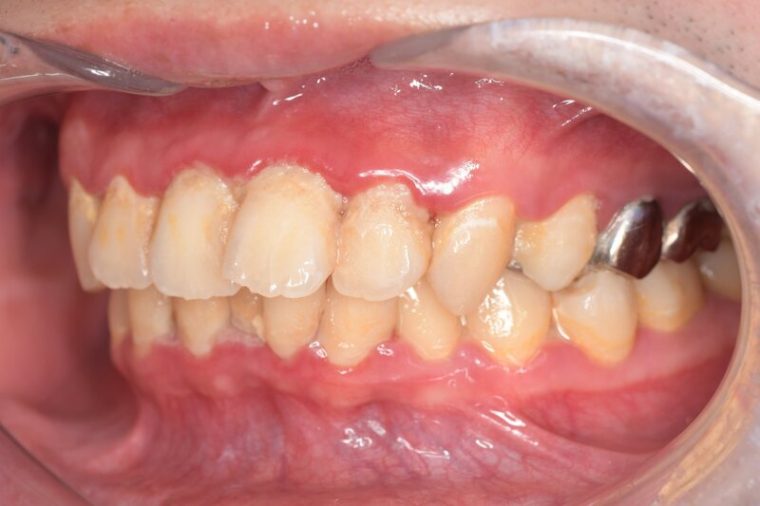

CASE 6

Before

After

基本情報

| 年齢・性別 | 35歳・男性 |

|---|---|

| 主訴 | 定期検診 |

| 治療内容 | スケーリング |

| 治療期間 | 30分 |

| 治療費 | 1,500円(保険診療) |

| リスク・副作用 | 知覚過敏、出血 |

| 治療方針 | まずは歯石除去を行い、ブラッシング方法の指導を行いました。炎症が落ち着いてきたら縁下歯石を除去して定期的なメンテナンスで歯石除去、着色除去を行います。 |

| 担当者所見 | 1年ぶりの歯医者。出血が多く炎症が強いため、歯石除去をしてご自身でもプラークコントロールができるようにブラッシングの方法をお伝えしました。 |